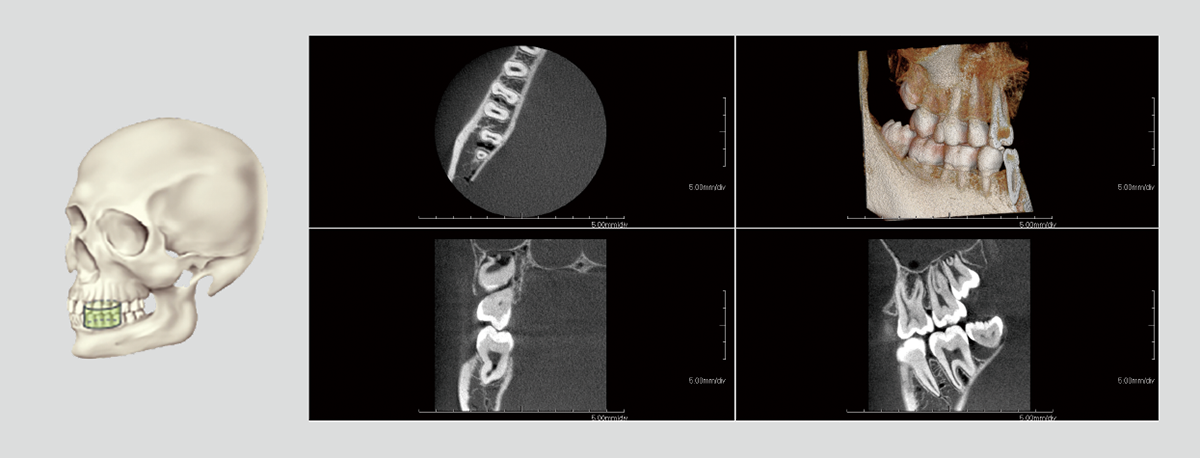

With dentists from various fields of expertise as advisors, we have carefully selected FOVs that are commonly used in clinical practice. In addition to the 3D analysis function for image detail sizes of 5x5cm, 10x10cm, 15x10cm and 15x16cm, the device features “True” and “Reconstructed” panoramic modes. With one of the largest FOVs on the market, the PreXion3D EXPLORER helps to develop the best therapy options, particularly in oral and maxillofacial surgery, airway analysis and orthodontics, as well as ear, nose and throat medicine. The use of a large 25.4x31.7cm FPD enables 15x16cm FOV scanning in one rotation.

The precise and high-resolution display of hard and soft tissue enables outstanding diagnostics and planning across all areas of modern dentistry and maxillofacial surgery. A large high-definition FPD allows all FOVs scanned in a single rotation without using stitching function.

With many 3D imaging systems on the market today, high-quality images are often accompanied by high radiation exposure. The PreXion3D EXPLORER offers balance of both aspects. The PreXion3D EXPLORER utilizes the industry’s smallest 0.3mm x-ray tube focal spot and voxel sizes from 0.07mm to 0.3mm for all FOV sizes. In addition, by adopting a high X-ray tube voltage of 110kV, pulsed X-ray irradiation, 16bit gray scale, and a newly developed large FPD, it simultaneously achieves high-definition image quality for a wide range of dental clinical practice and low radiation exposure for patient safety.

A combination of the words “volumetric” and “pixel”, a voxel is a three-dimensional volume element shaped like an isometric cube. The PreXion3D EXPLORER offers powerful imaging software with voxel sizes ranging from 0.07 to 0.3mm in order to maintain image quality.